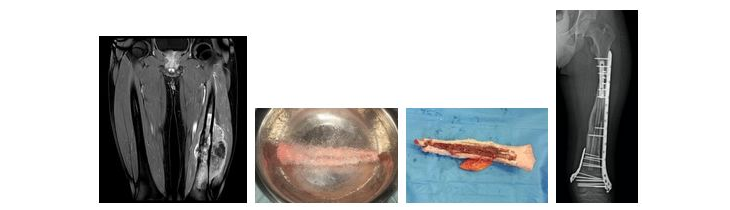

【骨・軟部腫瘍】

骨や軟部組織(脂肪組織や筋肉など)からできる悪性腫瘍は肉腫と呼ばれ、肺癌や乳癌といった悪性腫瘍(狭義のがん)とは区別されています。 肉腫はがんに比べると発生頻度が低いため非専門施設では経験が少なく、診断と治療が遅れることがあります。当科には骨・軟部悪性腫瘍、すなわち肉腫の診療を専門としたスタッフが2名おり、最新の画像診断と病理学部門の協力による病理組織診断をもとに、エビデンスに基づいた治療を行なっています。

悪性骨腫瘍の代表とされる骨肉腫やユーイング肉腫は小児期に多い疾患です。化学療法(抗がん剤治療)と手術が必要で、現在確立された標準的治療があります。 小児に対しては当院の小児科医の協力で化学療法を行い、われわれ骨軟部腫瘍外科医が手術、主に患肢温存手術を行います。四肢の関節周囲に発生することが多いため、腫瘍切除後の骨・関節の欠損による患肢機能低下が問題になります。

一般には腫瘍用人工関節を用いた再建術が行われていますが、当施設ではできうる限り術後の患肢機能を良好に保つことを目標に手術を行なっております。 例えば膝関節が温存できると判断した場合には関節面を残して腫瘍を切除し、切除した骨を液体窒素処理することで腫瘍を死滅させた後再利用する手法を選択します。関節面が残ることで人工関節と比べると良好な患肢機能が期待されます。

軟部肉腫に対しては手術による腫瘍広範切除術が原則です。術前に造影MRIにて腫瘍の進展範囲を十分に評価した上で切除範囲を設定します。切除により大きな筋肉や皮膚欠損が生じる場合があり、形成外科医のお力をお借りして筋皮弁形成術も併用しています。

また肉腫は全身のあらゆる部位に発生するため四肢以外の胸壁・腹壁など体幹部も手術の対象です。胸部外科や泌尿器科とも共同で手術に臨んでいます。不幸にも肉腫が進行すると遠隔転移(特に肺に多い)を生じることがあります。 全身化学療法や放射線照射などを駆使し、少しでも生命予後を改善すべく努力しています。このように東海大学では他科との連携により肉腫に対する集学的治療を行うことができます。

大腿骨骨肉腫に対する液体窒素処理骨と血管柄付き腓骨移植を組み合わせた再建術

膝窩部軟部肉腫切除後、遊離広背筋皮弁による再建術